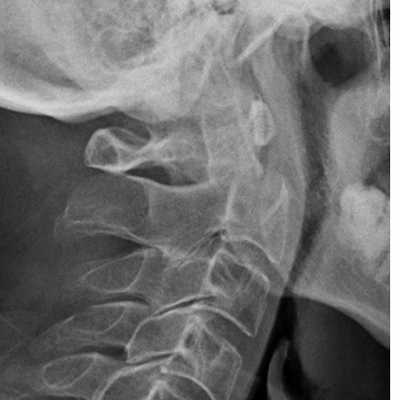

Перелом С2. Рентгенограмма в боковой проекции. Кольцо незамкнуто вследствие смещения зубовидного отростка назад.

Перелом С2 «повешенного». Рентгенограмма в боковой проекции. Смещение тела С2 вперед, отрыв задних элементов.